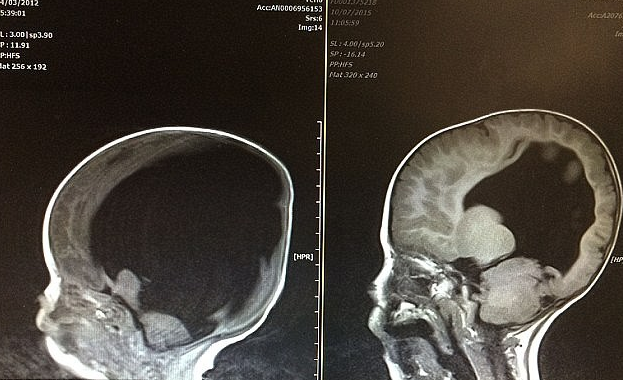

Hình ảnh X-quang hộp sọ của Noal. Bên trái là khi em mới sinh ra, não chỉ chiếm 2%. Bên phải là thời điểm 3 tuổi, khi bộ não đã "to ra". Ảnh: Caters News Agency

Tuy nhiên, cả Shelley và Rob Wall không từ bỏ ý định sinh con. Noal chào đời vào một ngày tháng 11-2012 trong tình trạng sức khỏe yếu và chỉ có 2% não trong hộp sọ. Phía bệnh viện từ chối hồi sức cấp cứu cho Noal.

Không phụ lại tình yêu thương của cha mẹ, Noal sống sót và phát triển một cách đáng kinh ngạc. Khi Noal được 3 tuổi, não của cậu bé đã tăng thêm bằng 80% so với kích thước não của đứa trẻ bình thường.

Thời điểm trước đó, các bác sĩ tin rằng Noal bị mắc chứng "tràn dịch não trong bụng mẹ" khiến não không phát triển, nhưng hiện nay họ cho rằng bộ não của cậu bé bị "nén lại". Khi cơ thể phát triển khỏe mạnh, bộ não đã "to trở lại" kích thước như vốn dĩ nó phải có.